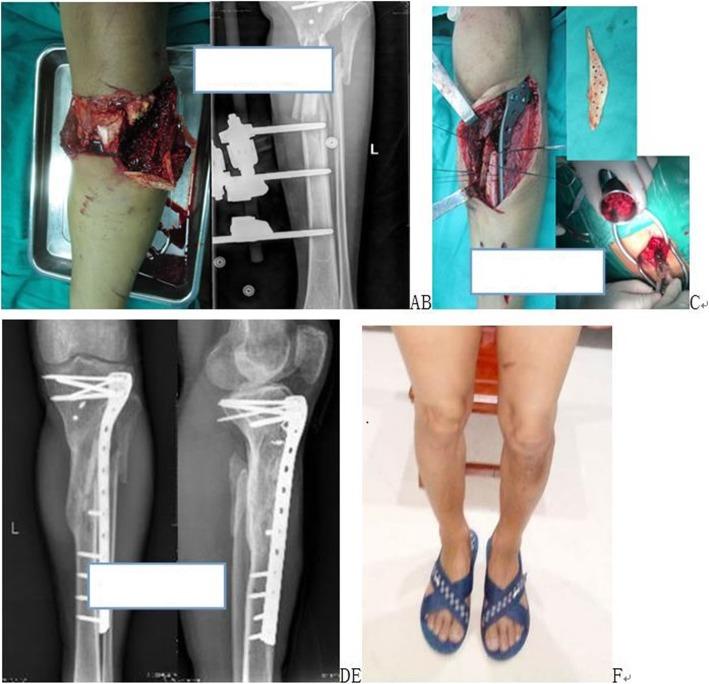

Application of multiple wrapped cancellous bone graft methods for treatment of segmental bone defects.

BMC Musculoskelet Disord. 2019 Jul 27;20(1):346. doi: 10.1186/s12891-019-2713-y.

[Application of meshy fascia encapsulating cancellous bone graft in repair of bone defect after limb fractures].

Zhongguo Xiu Fu Chong Jian Wai Ke Za Zhi. 2018 Dec 15;32(12):1530-1533. doi: 10.7507/1002-1892.201804071.

Similarities and Differences of Induced Membrane Technique Versus Wrap Bone Graft Technique.

Indian J Orthop. 2020 Jan 24;54(2):156-163. doi: 10.1007/s43465-019-00006-4. eCollection 2020 Apr.